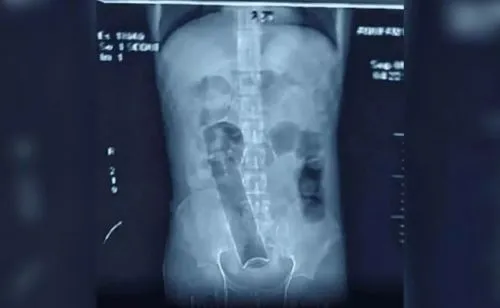

Allí, los médicos realizaron varias radiografías, que revelaron que tenía, por motivos que no trascendieron, una lata de desodorante de unos 20 centímetros inexplicablemente alojada en el colon, cerca del ano.

Según revelaron los informes, la lata estuvo dentro de su cuerpo durante 20 días, durante los cuales el hombre no pudo hacer sus necesidades. Los médicos creen que la vida del joven podría haber estado en peligro si no se hubiera presentado en el hospital.